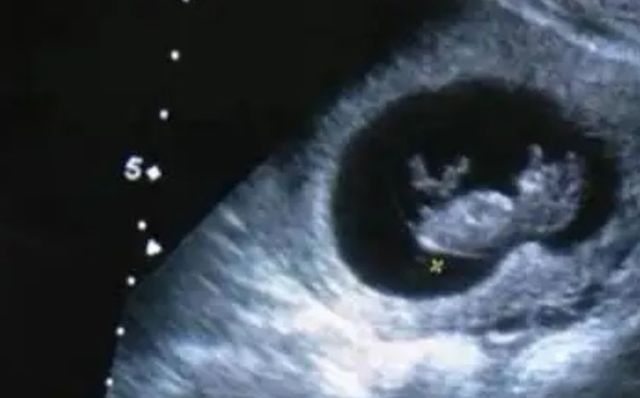

彩超检查

医生:拿着仪器放在你的肚子上

医生:恭喜你,胚胎发育很好,他现在拥有了胎心,以后会有越来越多的惊喜等着你

苏酒酒拍下照片

苏酒酒热泪盈眶,摸了摸肚子,宝宝谢谢你,这么坚强

苏酒酒他现在只有蓝莓那么大